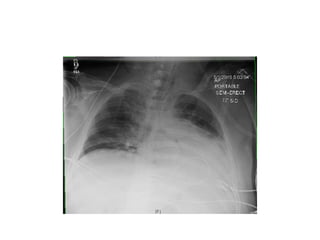

Patient comes in with this also

• What is the microbiological diagnosis?

Patient comes inwith this also • What is the microbiological diagnosis?